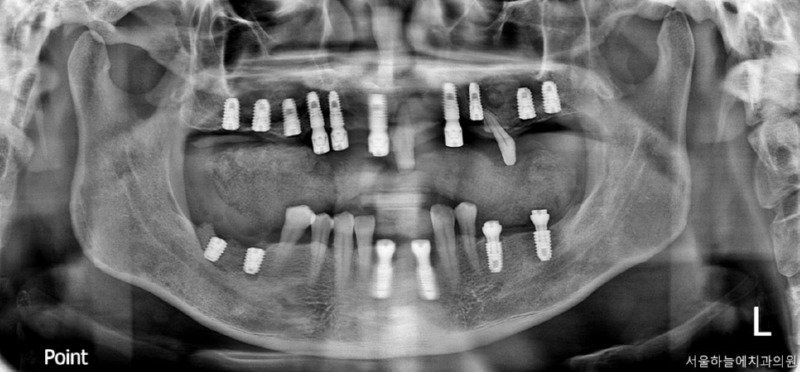

이 환자분은 다음과 같은 계획으로

치료를 진행했습니다.

· 수면마취(의식하 진정요법) 하에 진행

· 상악 양측 상악동 거상술 + 임플란트 10개 식립

· 하악 발치 후 결손 부위 포함 임플란트 6개 식립

수술 후 4개월